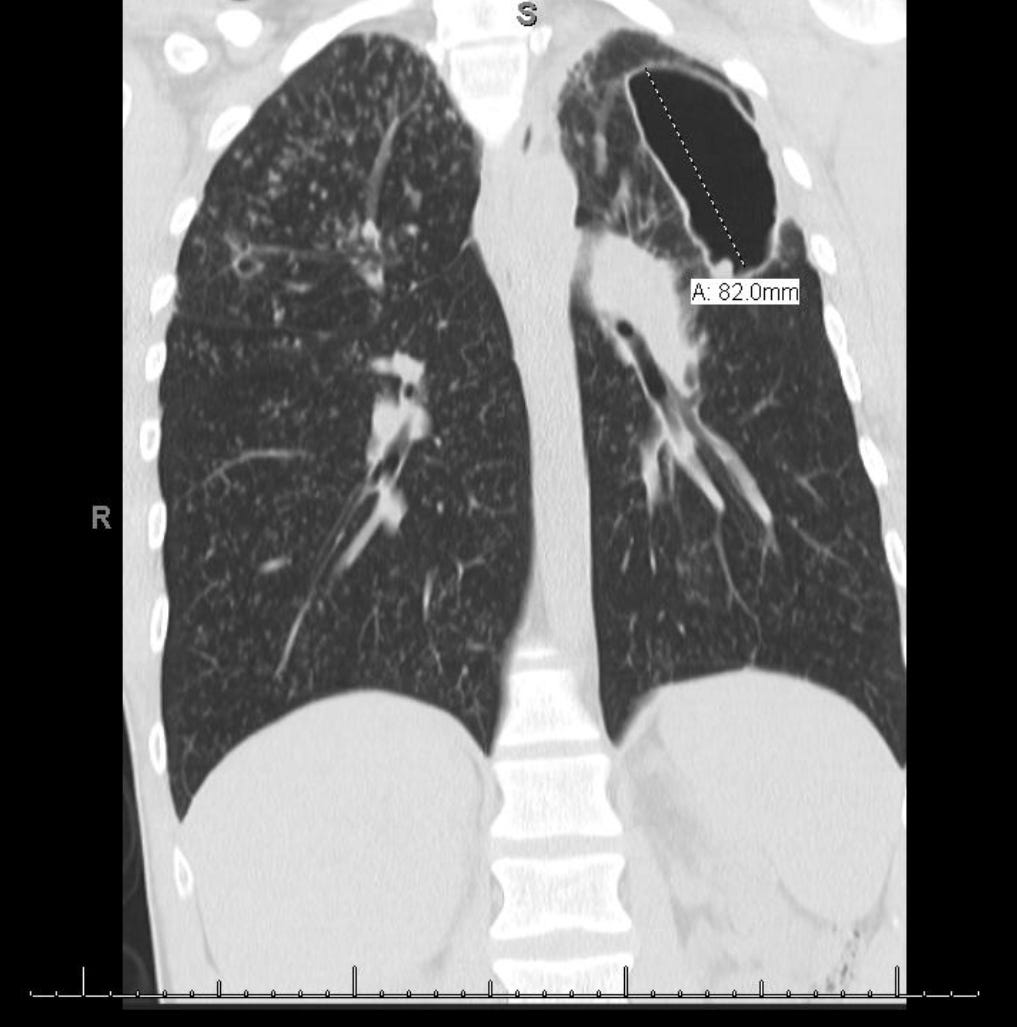

Chest computed tomography shows clustered centrilobular nodules (arrows Valley Fever Xray If you don't become ill or have symptoms from valley fever, you may only find out you've been infected later. Coccidioidomycosis, or san joaquin valley fever, is a systemic fungal disease with many potential clinical manifestations. Through a blood test, your doctor can check for antibodies against the fungus that causes valley fever. If doctors think you may. Those who. Valley Fever Xray.